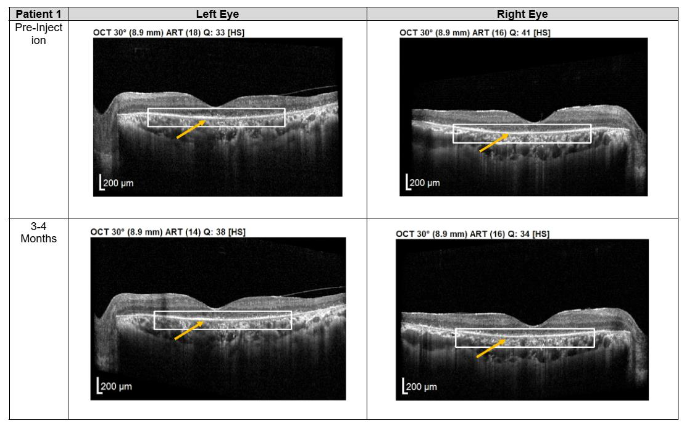

Both patients received a total of seven mesenchymal stem cell (MSC) transplantations, administered every 4-6 weeks, with follow-up from November 2020 to November 2022. Both patients reported no deterioration in vision since the first subtenon implantation in November 2020. Optical coherence tomography (OCT) images consistently demonstrated the maintenance of a hyperreflective region, with no notable increase in intensity. The previously reported improvements in visual function remained stable throughout the two-year follow-up, with no evidence of regression.

Figure 1. Optical coherence tomography (OCT) images for both eyes of Patient 1 from pre-injection up to 1 year follow-up. Orange arrow demonstrates the presence of hyperreflective material at the interdigitation area of the photoreceptors at the macula and extramacular region. These were observed and maintained until the last follow-up examination.

Importantly, no severe ophthalmic or systemic complications were observed during this period, supporting the safety of subtenon MSC therapy over a prolonged follow-up. No serious adverse effects were reported by either patient.